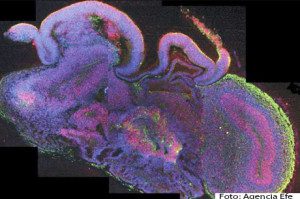

Londres .- Un equipo de científicos europeos ha desarrollado pequeños cerebros humanos tridimensionales, de cuatro milímetros de diámetro, a partir de células madre pluripotentes que ayudarán a profundizar en el estudio de las enfermedades neurológicas, informó hoy la revista científica «Nature».

Estos microcerebros, que incluyen la corteza cerebral que cubre los dos hemisferios, están formados por diferentes tejidos dispuestos en capas, cuya organización guarda muchas semejanzas con la de un cerebro en sus etapas más tempranas de desarrollo.

Para demostrar la utilidad de este sistema celular, los científicos analizaron las diferentes enfermedades neurológicas que tienen lugar cuando el cerebro se encuentra en pleno desarrollo, como la microcefalia.

A partir de células madre pluripotentes, el equipo de investigadores añadió al sistema inicial una serie de células procedentes de pacientes que padecían microcefalia para obtener un cerebro característico de una persona con esta enfermedad.

Los científicos encontraron así que en los cerebros con esta dolencia las células precursoras de las neuronas dejaban de proliferar demasiado pronto, un defecto que podría explicar algunas de las causas de la microcefalia.